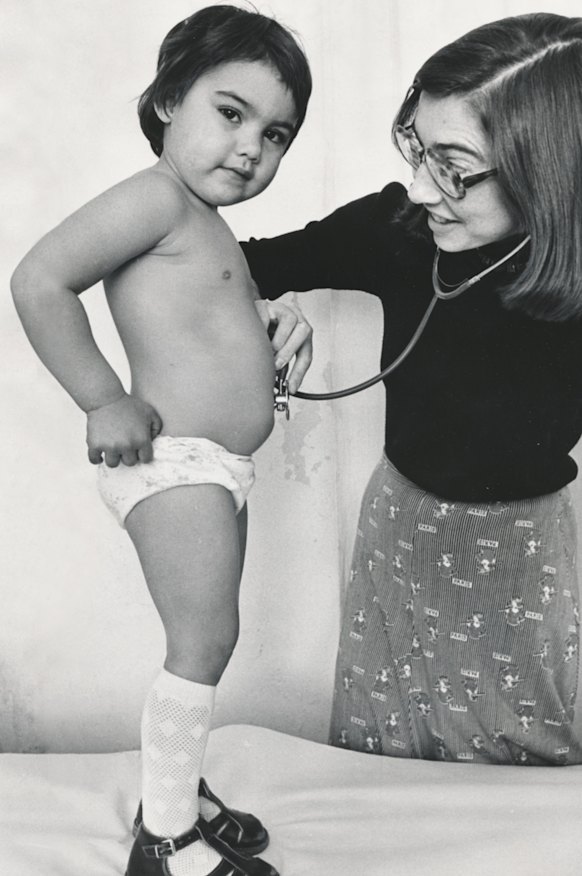

The future senator was there that day because three generations of women in her family had worked hard to establish the Aboriginal community-controlled health service from scratch: her remarkable great-grandmother Edna Brown, an elegant lady who raised money to save her people from pauper graves; her grandmother Alma Thorpe, a Gunditjmara activist who helped set up Aboriginal health services across the country; and her mother Marjorie Thorpe, a strong community leader who ended up running the Victorian Aboriginal Child Care Agency. “Lidia comes from a line of incredibly strong and very important Aboriginal matriarchs,” says Victoria University history professor Gary Foley.

In 1973, when Marjorie gave birth to Lidia as a 19-year-old single mother, she was pressured at the hospital to give her up for adoption. But Marjorie refused and four years later married Thorpe’s father, a white carpenter called Roy Illingworth. They separated when Thorpe was in early primary school.